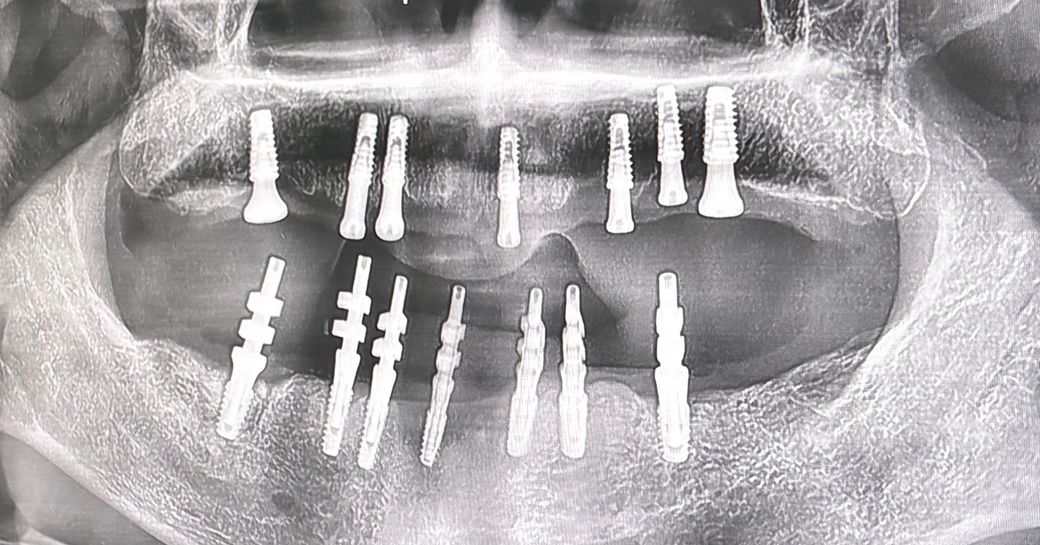

전악 임플란트 인 상태이시고 임시틀니 사용중이세요

하악만 abutment 만들기위해 imp 뜰 예정이라면 임시틀니 끼고 바이트를 뜨고

다음내원 시 어벗끼우고 크라운 제작하기위해 임프를 뜬다면

• 하악 어벗끼우고 바이트는 어떻게 채득해야하나요 ?

원래는 어벗위에 바이트 채득하자나요

똑같이 위아래 틀니끼우고 바이트 채드하는건가요..?

• 1번 째 사진

임플란트 최종 보철에 사용할 수 있는 정도의 정확한 치아배열의 임시틀니 상태면 임시틀니로 교합채득하면 됩니다.